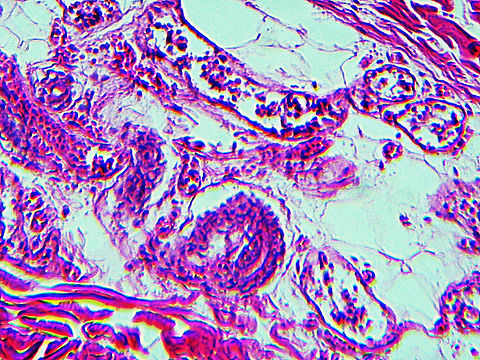

This slide is a skin biopsy from a person infected with Rickettsia rickettsii (the causative agent of Rocky Mountain Spotted Fever). It shows necrosis, vasculitis, and inflammation.

''Rickettsia rickettsii'' is a Gram-negative, intracellular, coccobacillus bacterium that is around 0.8 to 2.0 μm long. ''R. rickettsii'' is the causative agent of Rocky Mountain spotted fever. ''R. rickettsii'' is one of the most pathogenic ''Rickettsia'' strains. It affects a large majority of the Western Hemisphere and small portions of the Eastern Hemisphere.